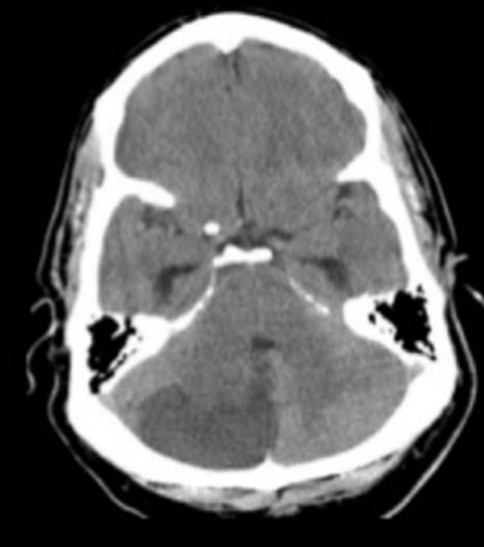

A 65-year-old man presents with ataxia, confusion and headaches.

Start Case